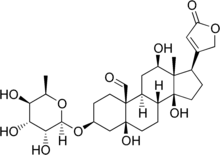

α-Antiarin | |

| IUPAC names

α-Antiarin: (3S,5S,8R,9S,10S,12R,13S,14S,17R)-5,12,14-trihydroxy-13-methyl-17-(5-oxo-2H-furan-3-yl)-3-[(2R,3R,4R,5R,6R)-3,4,5-trihydroxy-6-methyloxan-2-yl]oxy-2,3,4,6,7,8,9,11,12,15,16,17-dodecahydro-1H-cyclopenta[a]phenanthrene-10-carbaldehyde β-Antiarin: (3S,5S,8R,9S,10S,12R,13S,14S,17R)-5,12,14-trihydroxy-13-methyl-17-(5-oxo-2H-furan-3-yl)-3-[(2R,3R,4R,5R,6S)-3,4,5-trihydroxy-6-methyloxan-2-yl]oxy-2,3,4,6,7,8,9,11,12,15,16,17-dodecahydro-1H-cyclopenta[a]phenanthrene-10-carbaldehyde | |

| C29H42O11 | |

| Molar mass | 566.644 g·mol−1 |

Antiarins are cardiac glycoside poisons produced by the upas tree (Antiaris toxicaria).[2] There are two forms, α-antiarin and β-antiarin.

β-Antiarin, a cardiac glycoside steroid, can be isolated from upas tree latex (Antiaris toxicaria). Its use ranges from medical use, such as hypertension treatment, to arrow poison application. It also proves to be more poisonous than curare, sporting a low LD50 of 0.1 mg/kg in most mammals.[3]